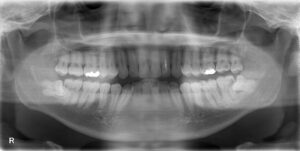

昨日、本日、親知らずの抜歯を行いました。

昨日行ったのは、画面向かって右下の親知らずです。

この親知らずの影響で手前の歯が大きな虫歯になっていました。

患者様とご相談の上、問題なく抜歯終了しております(^^♪